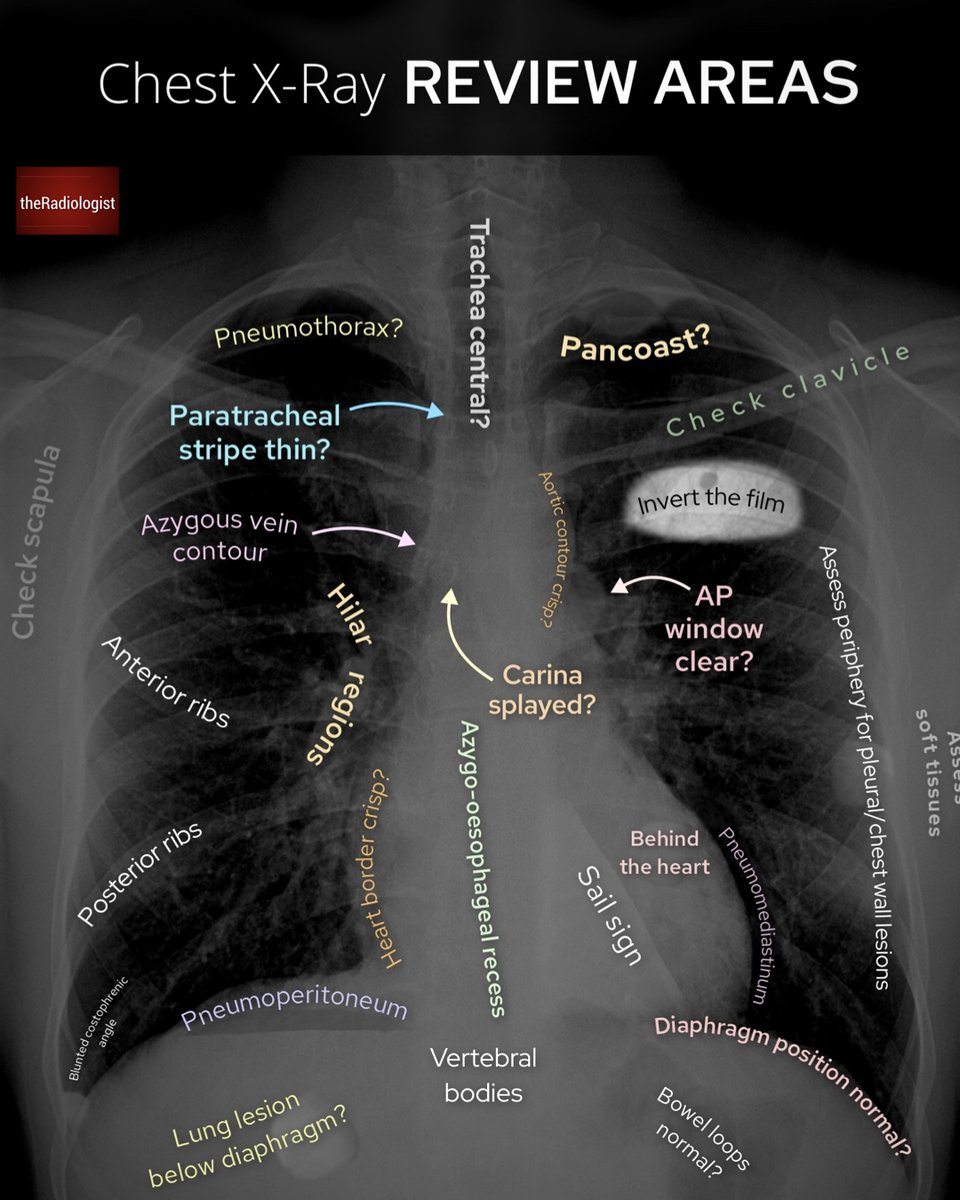

Chest X-Ray review areas